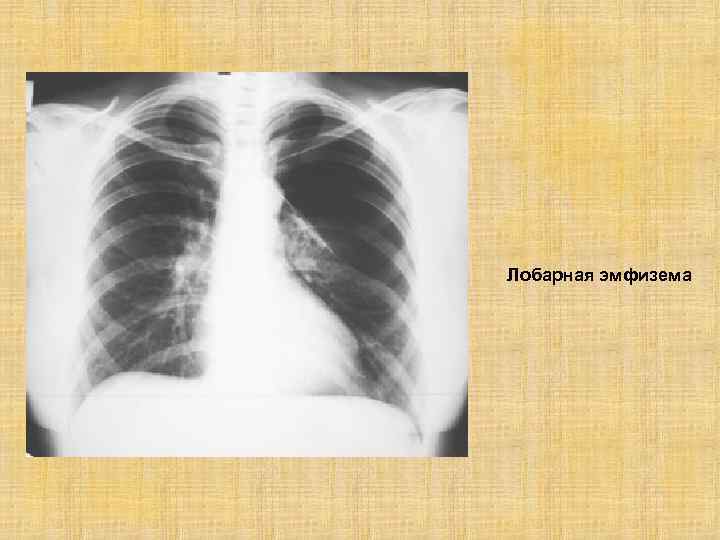

Рентгеновские снимки при врожденной эмфиземе легкого

Раздел: Визуальные уроки